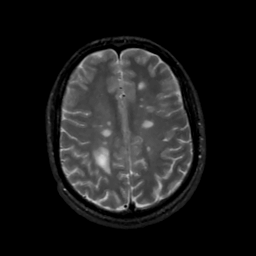

MR Study #8, March 31, 1991 -- Slice #35

[Home][Help][Clinical][Tour 1][Tour 2] Slice 35